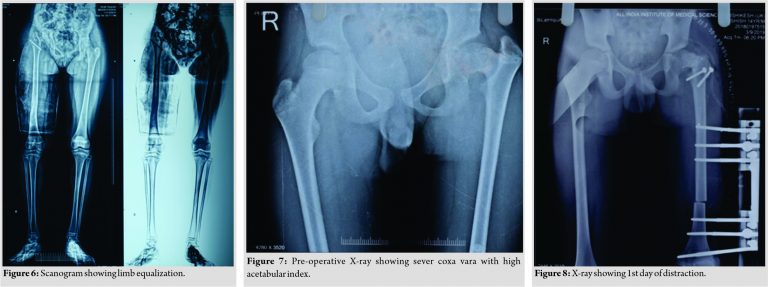

The second patient, a 14-year-old male, presented to us with complaints of limping in the left lower limb without any pain in the hip joint. He also had a history of septic arthritis in the left hip which was managed non-operatively in a village hospital. There was no history of trauma, weight loss, or tuberculosis. On examination, it was found that the patient had limited terminal hip ROM with severe restriction in hip abduction (25°). There was a true shortening of 6 cm in the left femur and the patient walked with abductor lurch without any ankle equinus with excessive flexion in the opposite knee. An X-ray revealed severe coxa vara on the left side with increased acetabular index (Fig. 7). There was minimal joint space narrowing medially. The femoral diaphysis was thin as compared to the opposite side. The power of the muscles around the hip and knee was comparable to the opposite side. Based on these findings, it was classified as a case of Choi’s Type 2 septic sequelae of the hip with 6 cm of femoral shortening. The patient underwent trochanteric advancement distally as described in the previous case along with a simultaneous application of monorail external fixator and corticotomy in the distal femur. The distraction started on the 5th post-operative day in equal increments of 0.25 mm every 6 hourly (Fig. 8 and 9). After achievement of limb length equalization, the fixator was removed after 114 days. Three weeks after this, the patient presented with a fracture of the regenerate with minimal angulation and was managed further by one and a half spica cast for further 4 weeks (Fig. 10). At latest 12 months follow-up, the patient was walking normally with minimal abductor lurch.